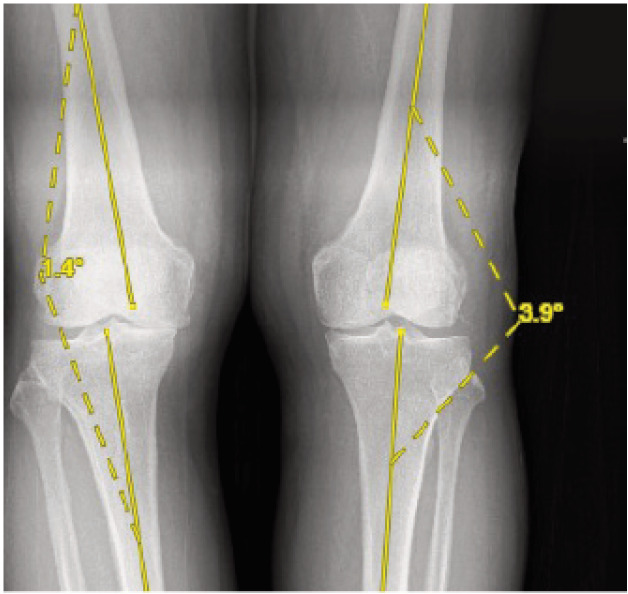

Materials and methods: A prospective cohort study on patients with knee osteoarthritis receiving treatment in a single tertiary hospital was conducted. All patients consented to participate in this study. Patients were assessed functionally with the Western Ontario and McMaster Universities Osteoarthritis Index (WOMAC) and radiologically with plain radiographs. Patients were subjected to undergo both supine and standing plain radiographs of the knee in the same setting for comparison purposes where measurement is done following patient functional outcome and radiological measurement for the patient.

Results: Our study shows that reduction in joint space is more obvious in weight-bearing radiographs, however in severe or higher-grade osteoarthritis, a supine radiograph is adequate to diagnose knee osteoarthritis.

Conclusion: Standing radiograph of the knee is preferred to a supine knee radiograph wherever possible due to the additional value it brings, however, in certain patient conditions, a supine radiograph is still acceptable.